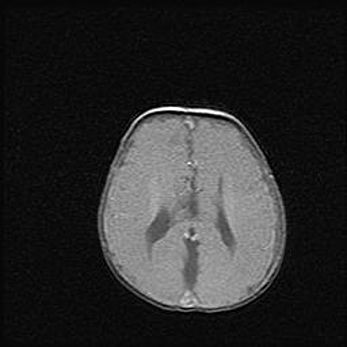

Церебральная ишемия II.

Возраст: 5 дней

Вес: 3400 г

Пол: женский

Окружность головы: 35 см

Срок гестации: 39 недель

Церебральная ишемия – это заболевание, характеризующееся недостаточностью (гипоксией) либо полным прекращением (аноксией) снабжения мозга кислородом по причине закупорки одного или нескольких сосудов. Это приводит к  что метаболическим расстройствам различной степени тяжести в тканях головного мозга, развитию коагуляционных некрозов и гибели нейронов.